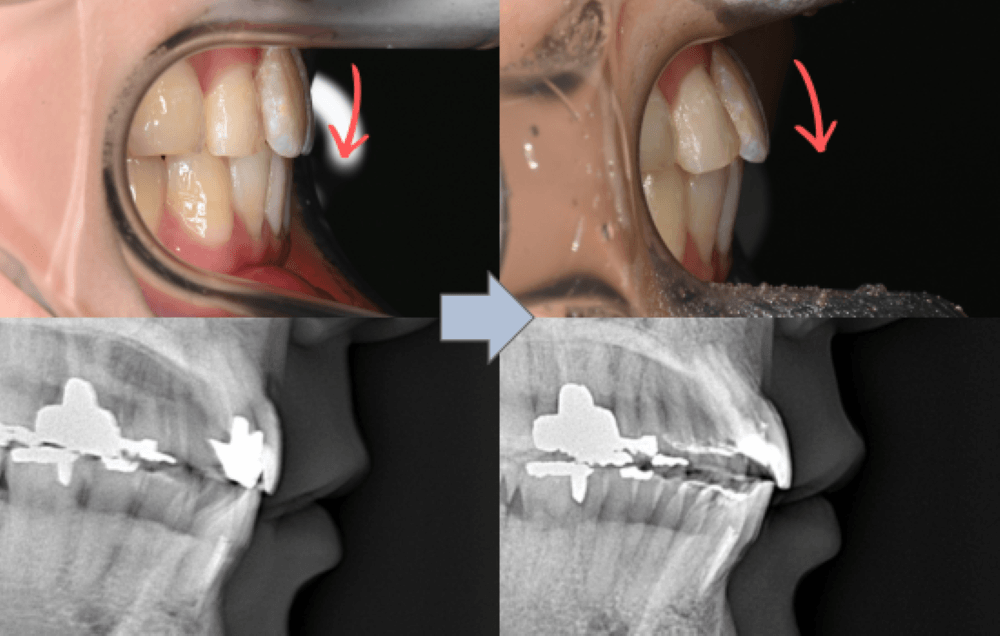

前歯の傾斜(Interincisal angle)

レントゲンの計測値で、上下前歯のなす角度は 138° でした。

一般的な平均値(約128°)と比較すると角度が大きく、上下の前歯が内側へ倒れ込んだ状態であることが分かります。この状態では前歯が奥へ引き込まれて見えやすく、口唇の支持が弱くなることがあります。

治療後は、舌側に倒れていた前歯の傾きが改善しています。

・上下前歯のなす角(Interincisal angle)

138° → 125°

前歯のポジションが適正化されたことで、スマイル時に奥まって見えていた歯の見え方が改善し、より自然な印象になっています。

また、唇を内側から支える「口唇サポート」が回復し、横顔の印象にも変化がみられました。